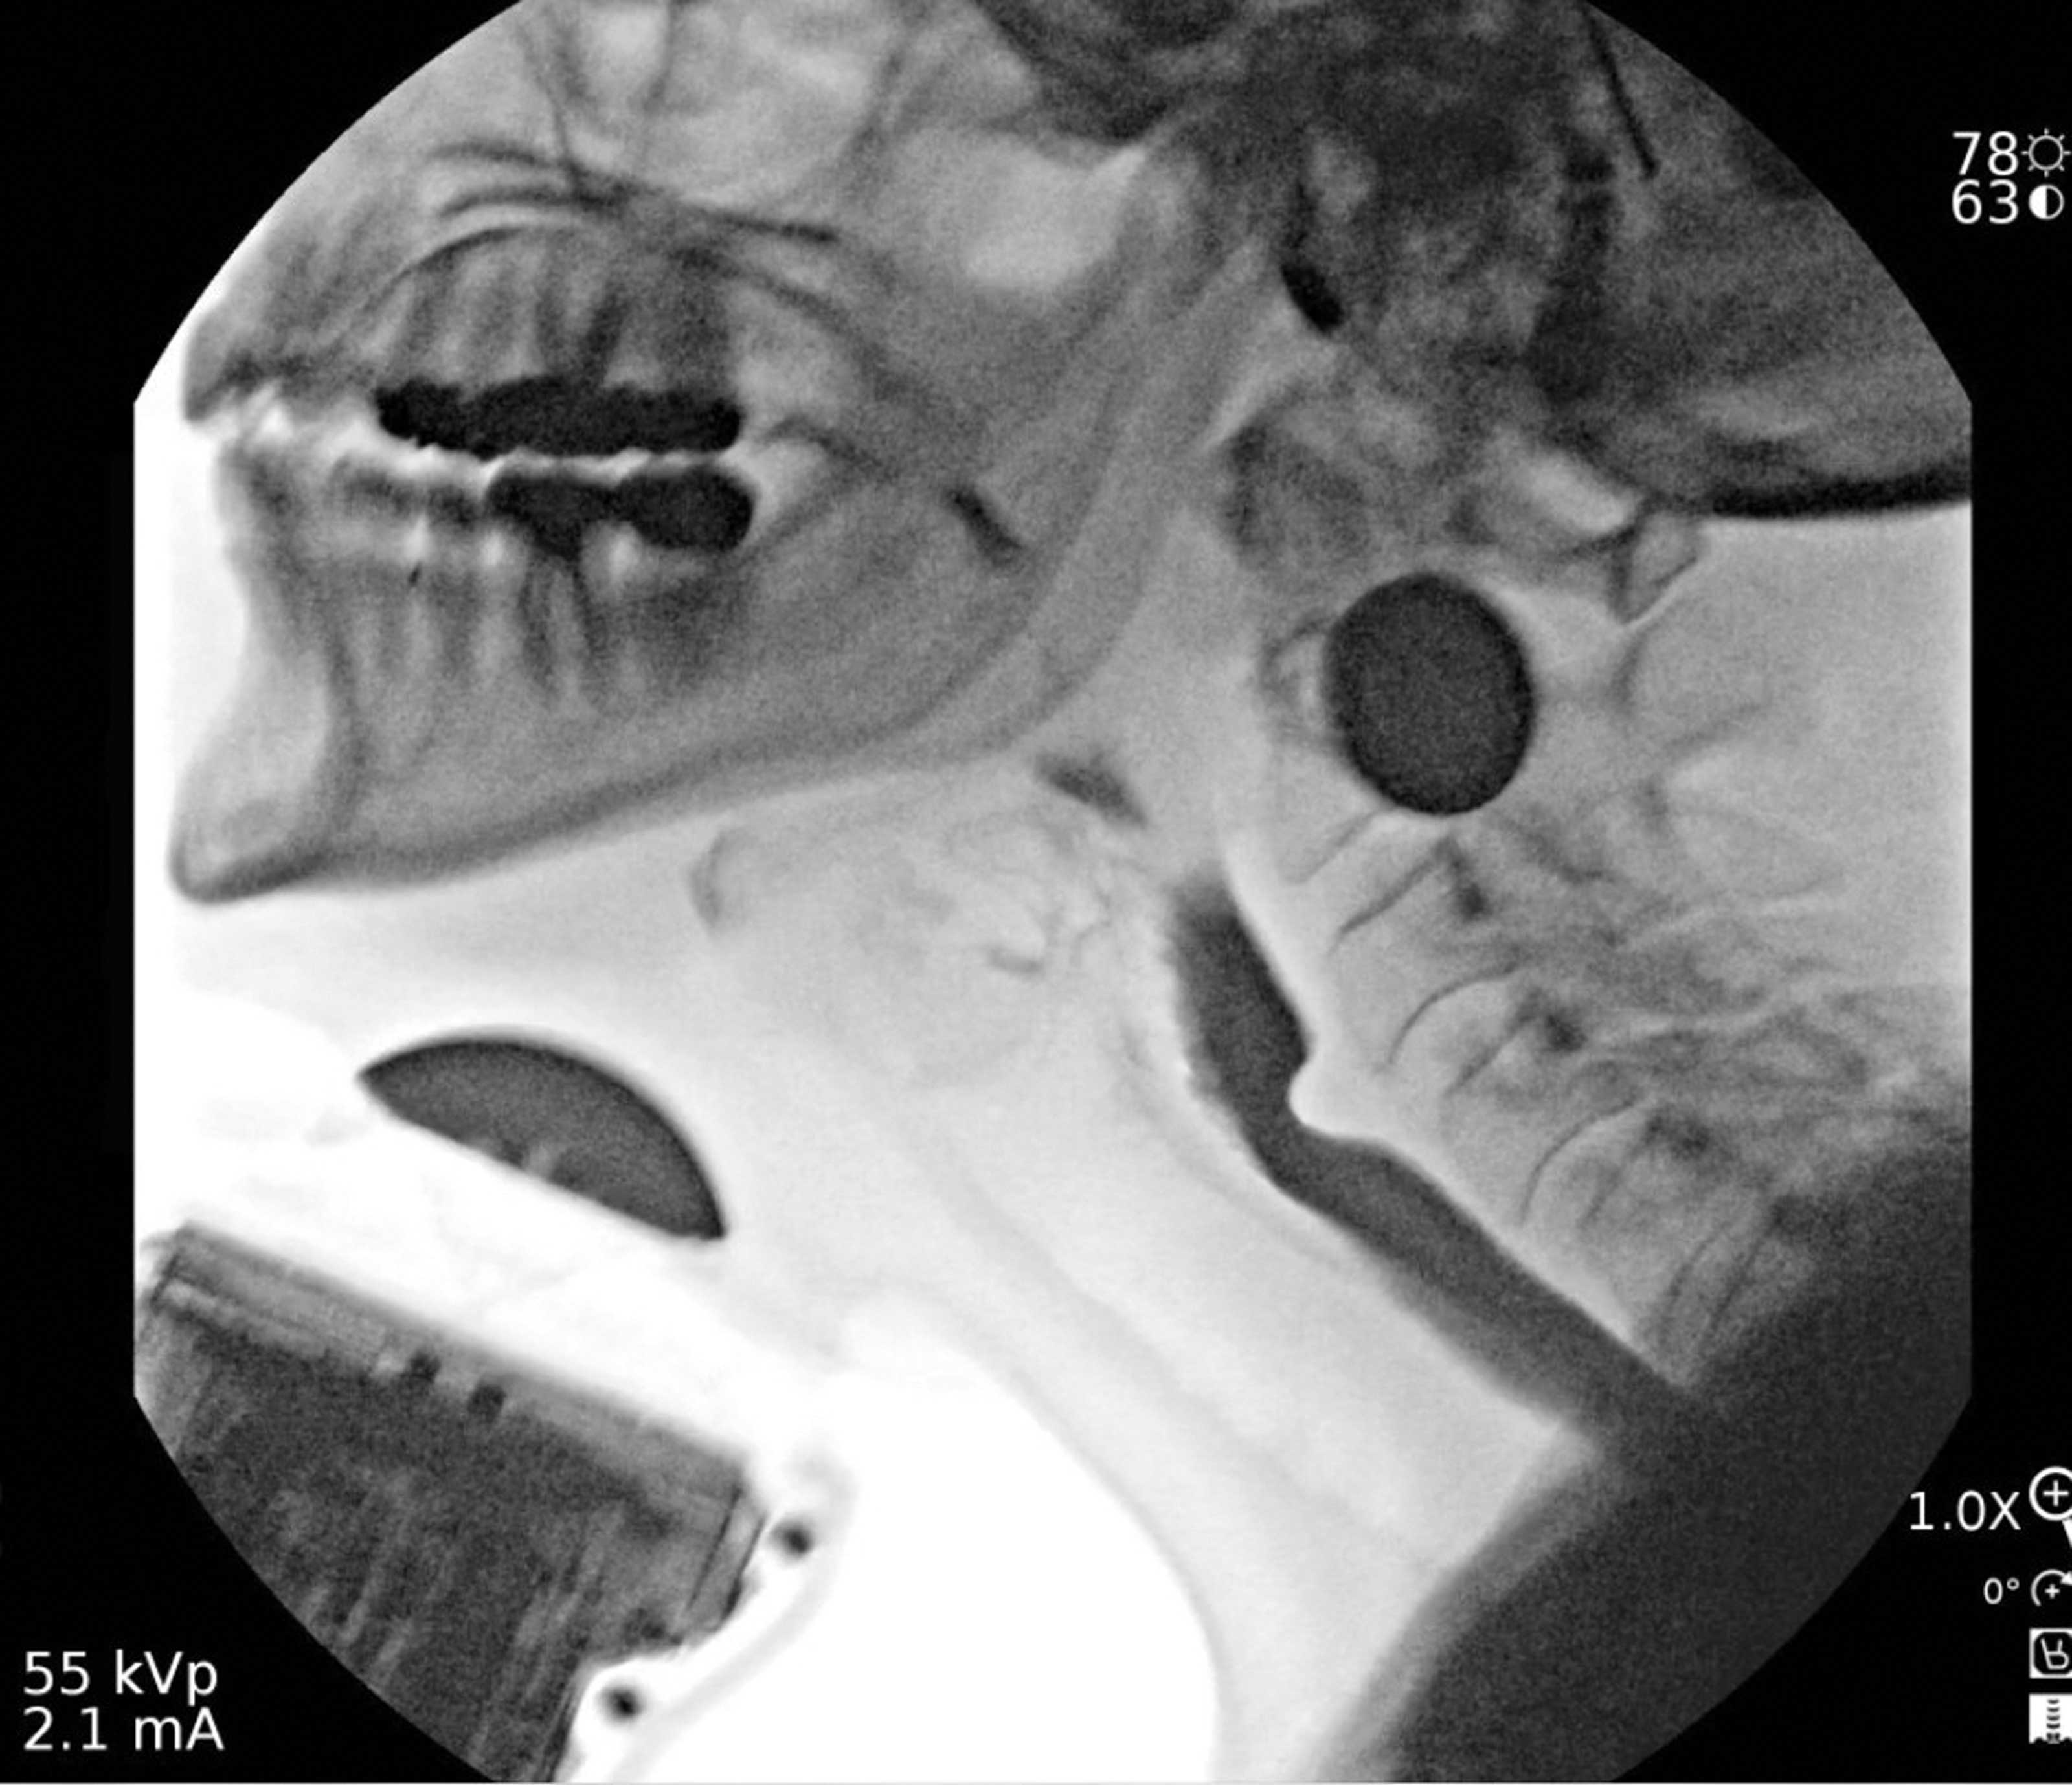

Scarless thyroidectomy: the RABIT journey in robotic innovation

Surgeons in Bangalore share how a novel robotic approach enables scar-sparing thyroid surgery for large nodules and cancer, while reshaping global training. Can an 8 cm benign thyroid cystic nodule be removed without a big scar in the neck? Can...